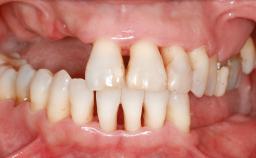

Ridge Preservation and Implant Placement for a Fixed Dental Prosthesis After a Car Accident

It is well known to clinicians that any removal of teeth will, over time, cause the dimensions of the alveolar ridge to be reduced by resorption of the bundle bone and by changes related to external modeling. This development is particularly evident in the crestal region with its thin buccal bone that consists of bundle bone almost entirely. The facial bone will rapidly resorb as blood supply from the periodontal ligament gets disrupted (Araújo and Lindhe 2005). There is no reason why traumatic tooth loss should not have the same consequences. It takes more than achieving implant osseointegration for a treatment outcome to be considered successful. No deficiency of bone or soft tissue is acceptable when an ideal esthetic outcome is the goal. Several articles (Sanz and coworkers 2011; Vignoletti and coworkers 2011) have reported on techniques of improving the alveolar ridge for implant treatment, notably focusing on protecting tissues from resorption.

Case Type Extended Space

# of Teeth 6

Bone Volume Horizontally and vertically sufficient Horizontally deficient Deficient vertically or deficient vertically AND horizontally